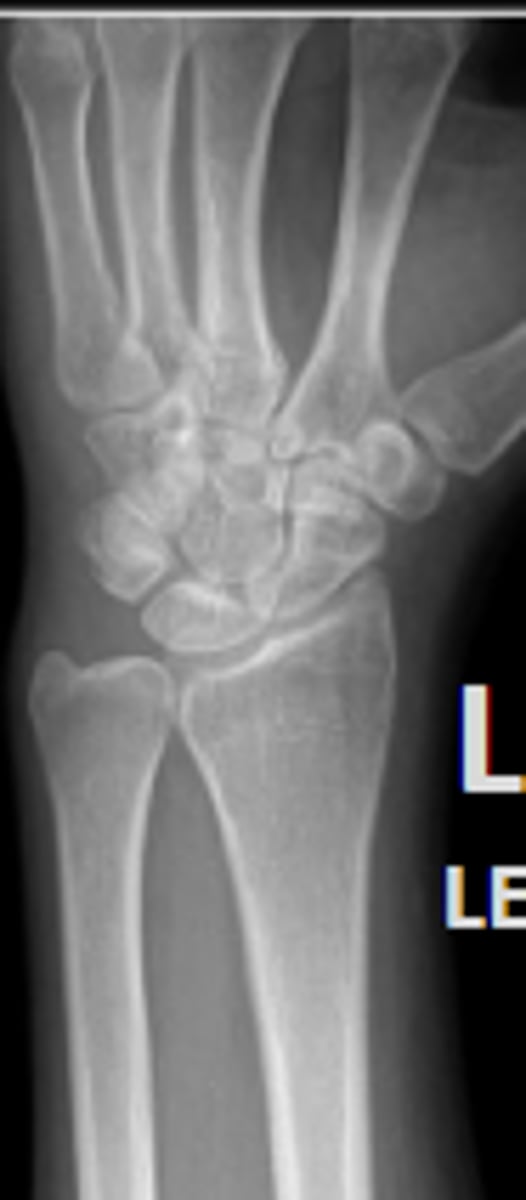

Medial oblique of the left wrist

What is the name of the radiographic view?